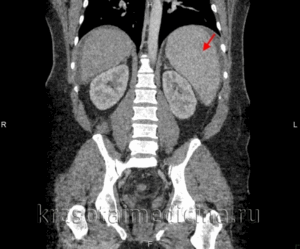

- компьютерная томография (Т);

- мультисрезовая компьютерная томография (МСКТ);

Помимо ультразвукового исследования, спленомегалию удается диагностировать с помощью компьютерной томографии, однако для малышей такая методика проводится в исключительных случаях ввиду высокой рентгеновской нагрузки на организм.